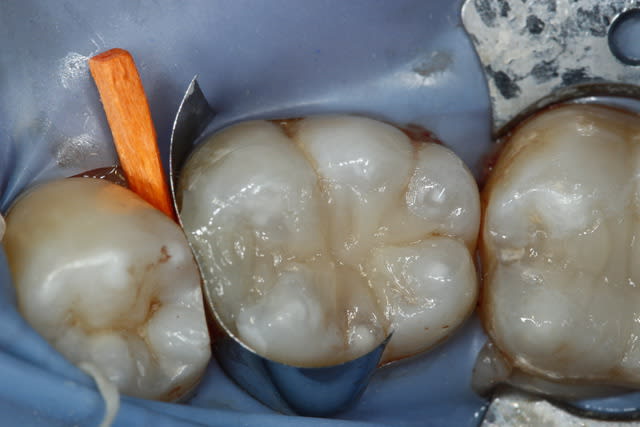

2 retraitements endo sur 45 46.

2 m85na9 - Eugenol

3 j2ewih - Eugenol

4 mbyxz8 - Eugenol

1 ojgvk3 - Eugenol